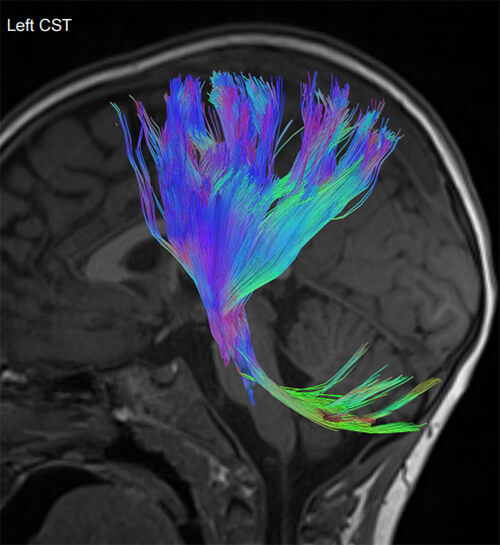

- Special state-of-the-art techniques (fMRI, Multiparametric MRI, Spectroscopy, Tractography, Dynamic Angiography, Neurography, CSF Flow Study)

- Τractography